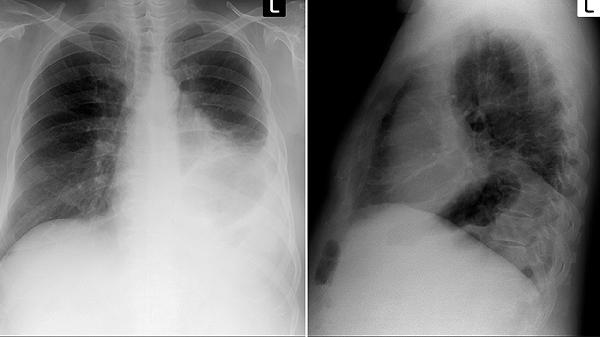

左肺下叶小结节是否严重需结合结节特征判断,多数为良性病变,少数可能与感染、结核或肿瘤相关。小结节通常指直径小于10毫米的病灶,需通过定期随访或进一步检查评估性质。

肺部小结节多为陈旧性炎症、钙化灶或良性增生,与长期粉尘接触、既往感染史等因素有关。这类结节边缘清晰、形态规则,随访中大小稳定,无须特殊处理,建议6-12个月复查一次胸部CT。若结节伴随咳嗽、胸痛等症状,可能与活动性感染相关,需结合痰培养等检查明确病因。

少数情况下,结节增长迅速、边缘分叶或伴有毛刺征,需警惕恶性可能。长期吸烟史、家族肿瘤史等高危人群若发现磨玻璃样结节,应缩短随访间隔至3-6个月,必要时行穿刺活检或PET-CT检查。早期肺癌的结节通常无明显症状,及时干预可显著改善预后。